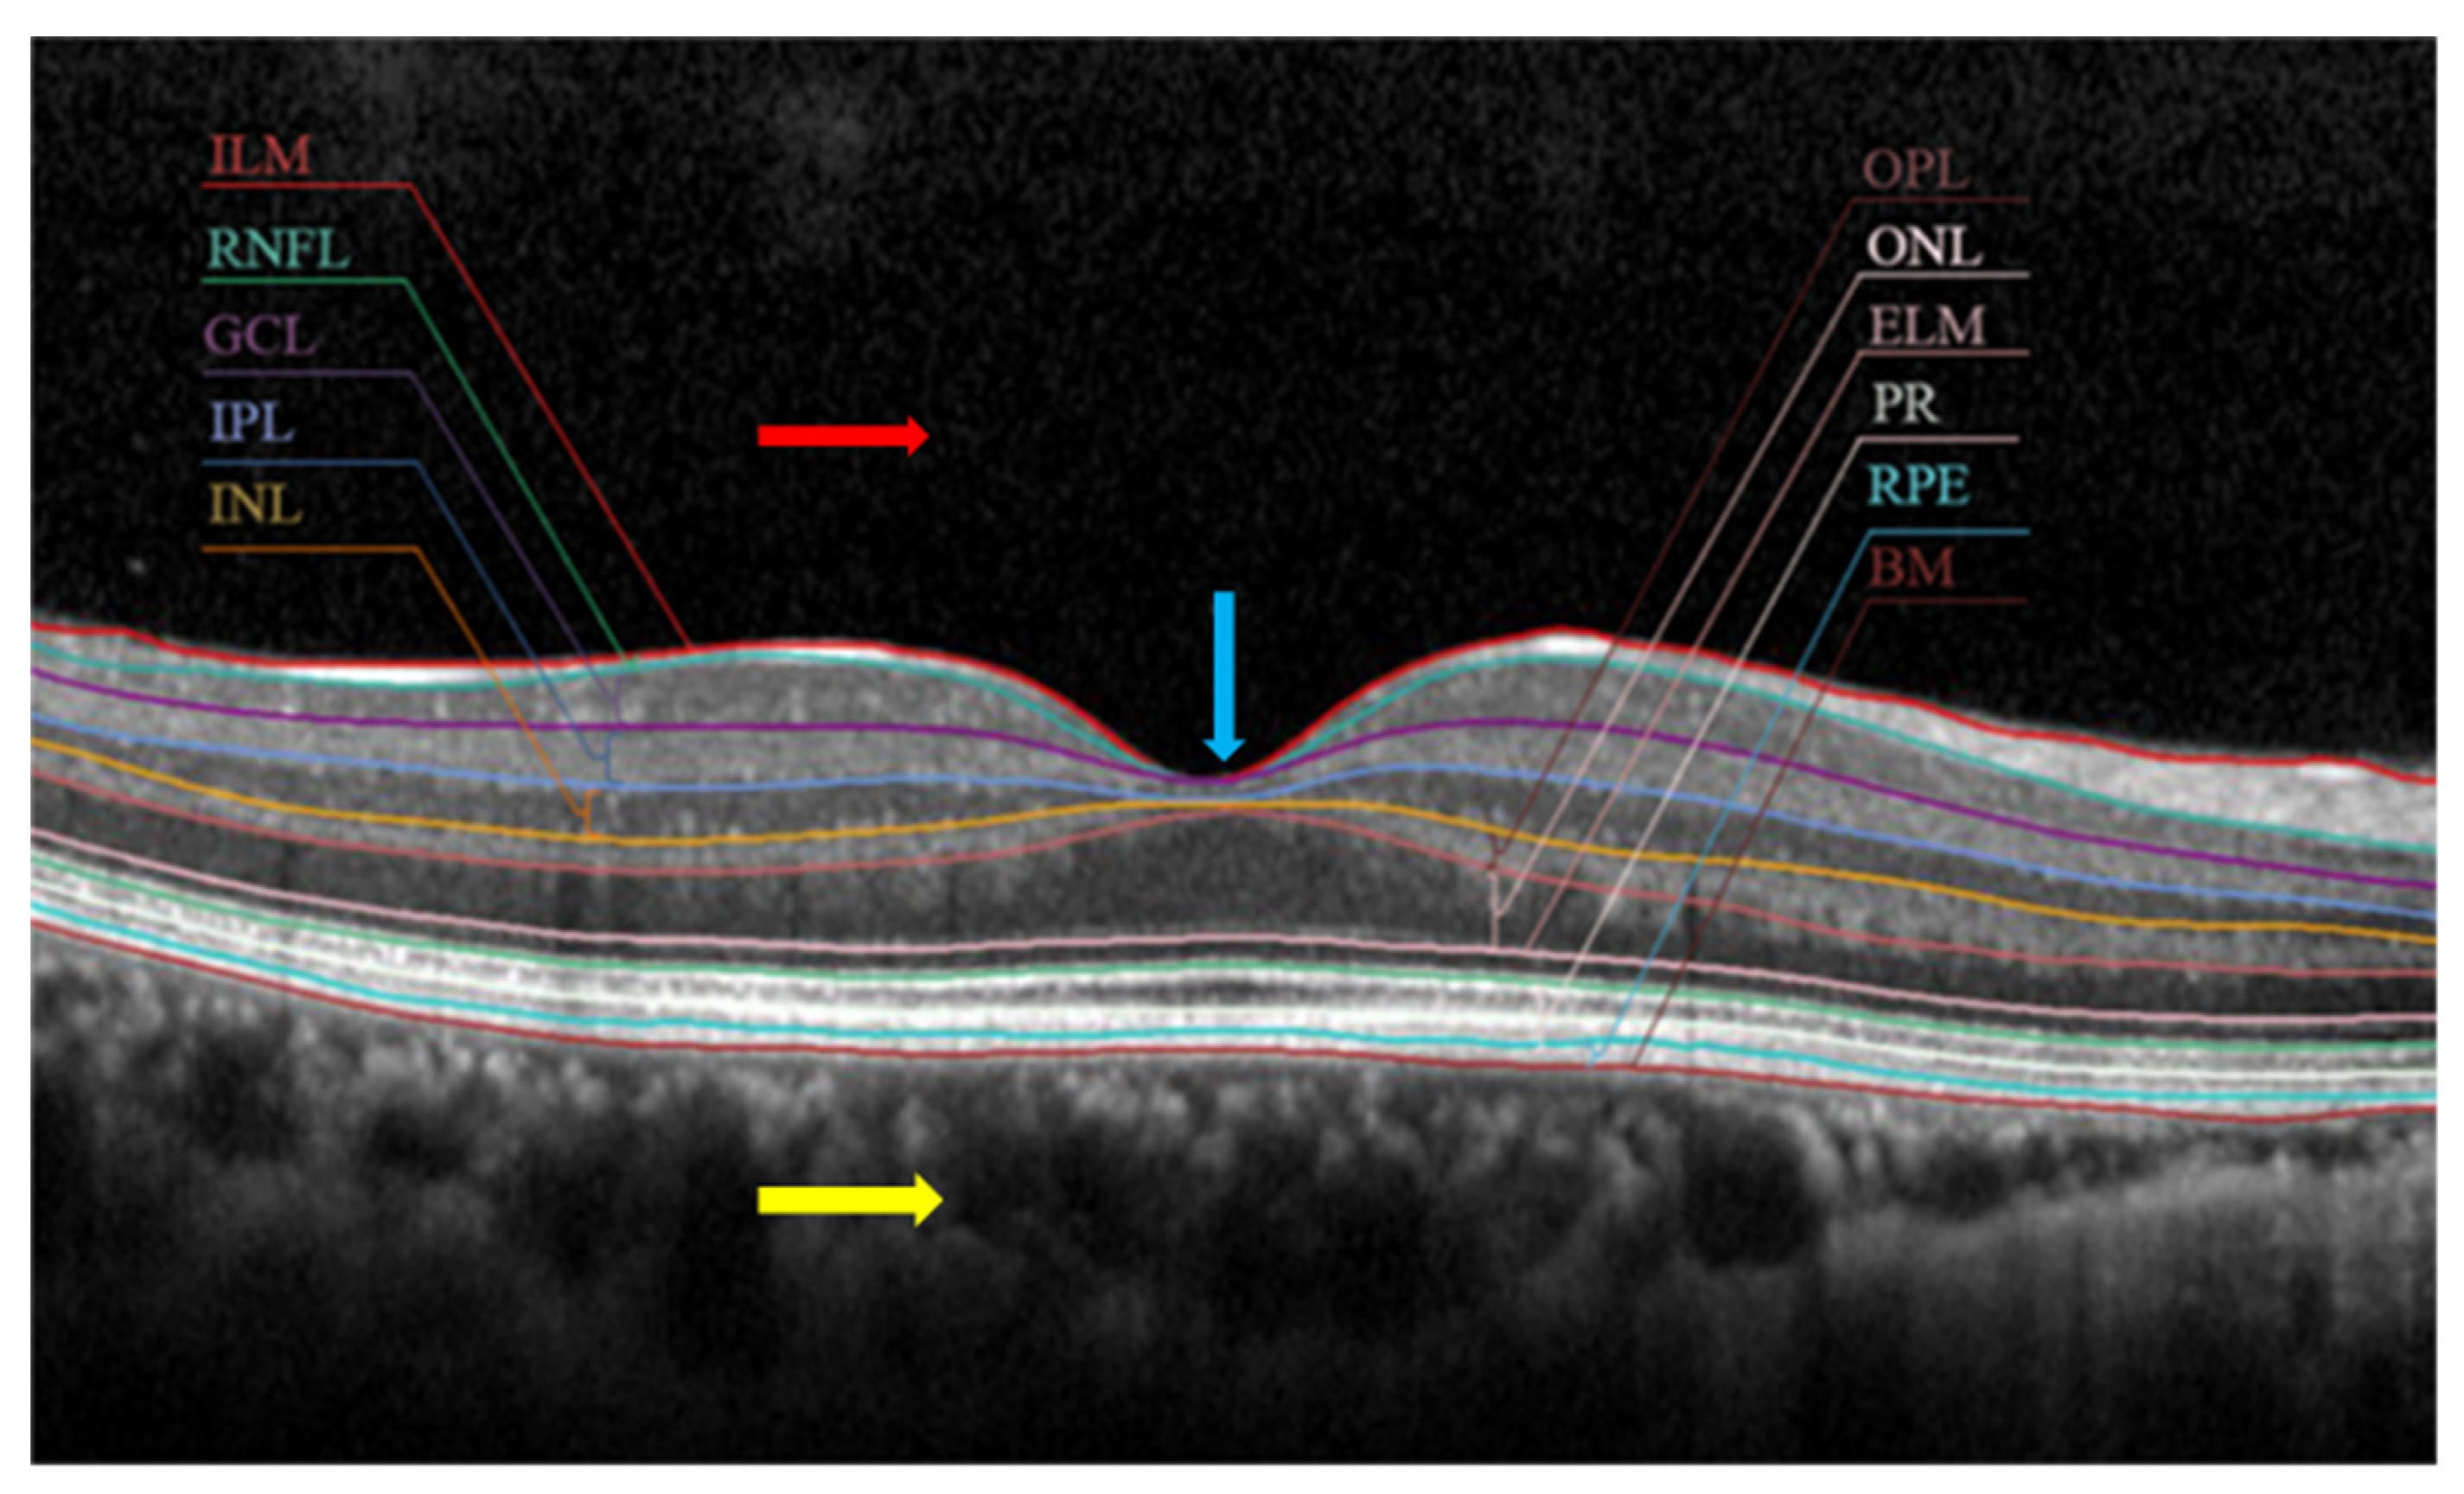

| Biomarkers | Association of the Biomarkers with the Eye Disease |

|---|---|

| Layer thickness | Changes in the retina’s thickness and its layers are characteristics of many diseases such as glaucoma and age-related macular degeneration (AMD). For example: a glaucoma patient has 20% lower RNFL (retinal nerve fibre layer) thickness than normal patient |

| Inner retinal lesion | A characteristic finding in various stages of diabetic macular oedema (DME) that is a key risk factor for developing more advanced stages of DME. |

| Drusen | A characteristic finding of the early stages of AMD that is a key risk factor for the development of more advanced stages. |

| Cup–disc ratio | A cup–disc ratio of more than 0.5 is a risk sign of glaucoma. |

| PVD | An early sign of macular 0edema and lamellar macular hole |